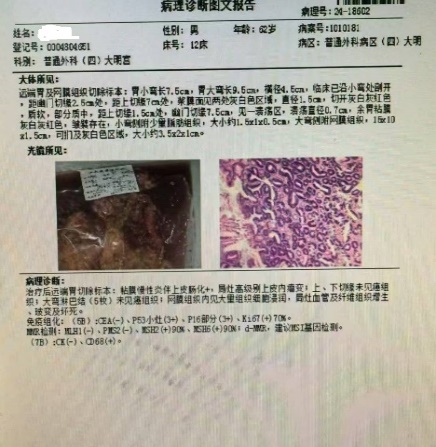

经过7个多月“漫长的等待”,患者于2024年7月再次入住老年普外科大明宫院区,术前再次行上腹部增强CT结果:胃窦壁稍厚,并浆膜外渗出性改变;横结肠局部壁厚,周围软组织增多,术前分期cTxNxM0,治疗后降期明显,已经符合手术根治性切除标准,如图二的CT所示。术前老年病MDT评估患者情况良好。做好术前准备后在大明宫手术室和麻醉科的配合下,2024年7月23日由科室主任王志东教授主刀,李运浩博士,金鑫住院医师协助进行完全腹腔镜下远端胃癌根治术,手术顺利,术后恢复顺利。术后病理显示胃癌病灶和淋巴结转移完全消失(图四所示),达到了医学上称之为的病理完全缓解(pCR)。知道这个结果后病人和家属都皆大欢喜,悬着的心终于放下了。术后1月来院系统复查仍然未见肿瘤复发和转移迹象,并再次进行了辅助治疗后顺利出院。

2024年7月术后病理结果 胃原发灶和淋巴结癌灶消失

据老年普外科主任王志东教授介绍,胃癌术后病灶活检消失-即病理完全缓解(pathological complete response,pCR)是指在接受新辅助治疗或者转化治疗后的胃癌切除标本中,大体观察未见明显肿瘤残留,且在原发肿瘤区域广泛取材,镜下也未见肿瘤细胞残留,部分病人淋巴结也未见转移肿瘤细胞。本例病人胃癌的原发灶和淋巴结都未见到肿瘤细胞,说明我院对晚期或者进展期的胃癌诊治水平整体迈上了新的台阶。那么获得pCR的胃癌患者属于治愈吗?研究显示这只是预后良好的指标之一,并非完全治愈。目前的报道发现胃癌新辅助或者转化治疗后获得pCR的部分患者还会发生复发转移,尤其容易发生肝转移或脑转移,并且有些pCR患者预后比非pCR的患者更差。因此胃癌术后pCR不能简单等同于治愈,不能因为病理学上的完全缓解而放弃根治性手术和术后辅助治疗、忽略术后定期随访监测等。该病例的成功也反映出老年普外科对老年肿瘤病人采取肿瘤多学科和老年病多学科综合评估及诊疗迈上了新阶段。